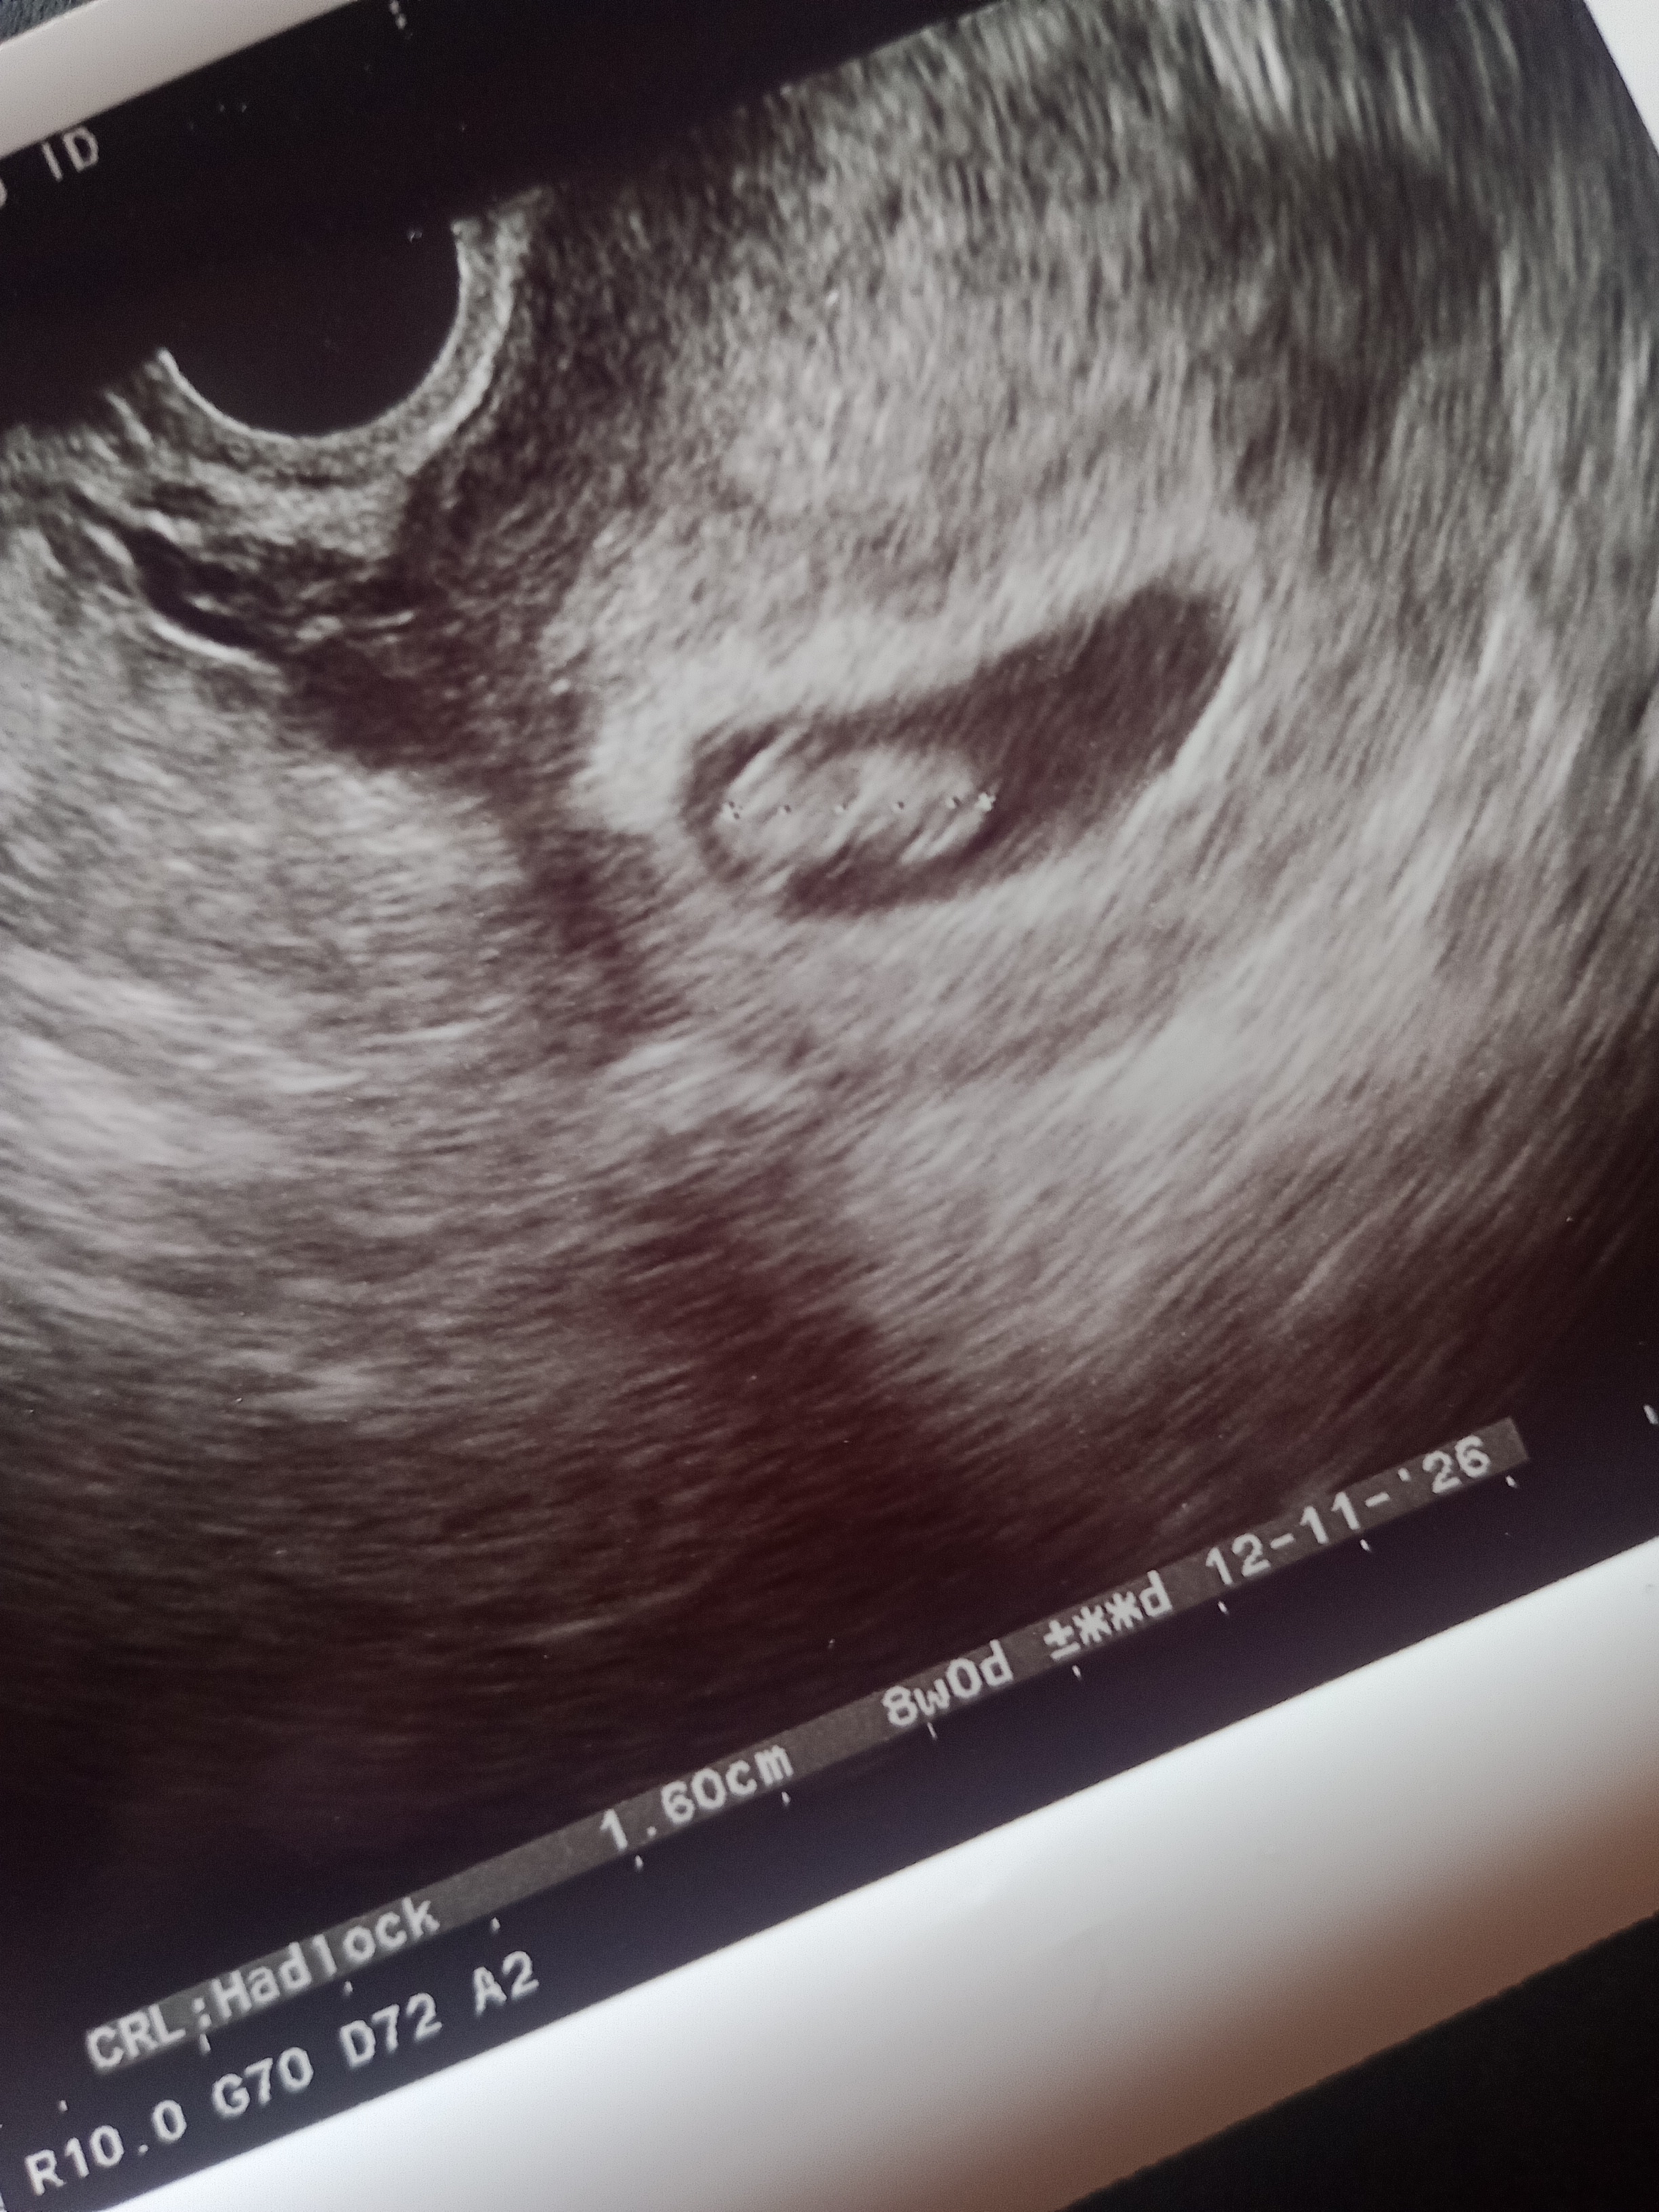

Bardzo mi przykroPęcherzyk zmniejszył się w porównaniu z pierwszym USG, na USG w szpitalu zmienił położenie. Krwi sporo, jakbym dostała miesiączkę. Niestety jestem w trakcie poronienia, w domu już poczułam jak skrzepy ze mnie wychodzą.

Bardzo mi przykro…Pęcherzyk zmniejszył się w porównaniu z pierwszym USG, na USG w szpitalu zmienił położenie. Krwi sporo, jakbym dostała miesiączkę. Niestety jestem w trakcie poronienia, w domu już poczułam jak skrzepy ze mnie wychodzą.

Hej. Nie nastawiaj się negatywnie. Jest pęcherzyk i ciałko żółte co oznacza że niedługo się pojawi zarodek.Tak nawet mówił mój lekarz jak przyszła i też to było widać. Pozatym wcześniej sama pisałaś że pewnie przesunęła Ci się owulacja więc ciąża młodsza pewnie. Co mówi lekarz ?Hej dziewczyny. U mnie chyba niestety znowu nic z tego nie będzie. Jest pęcherzyk i ciałko żółte niestety zarodka nie widać. Lekarz kazał zbadać przyrost bety bo mówi że przy naturalnych ciążach takie rzeczy się zdarzają, ale ja się przestałam już łudzić.